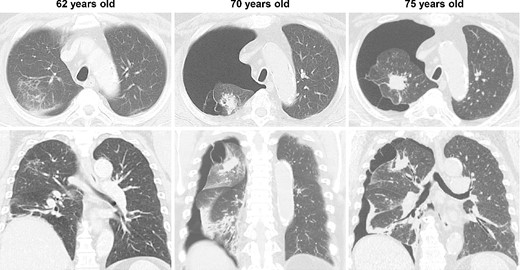

CT images of the intervening period between the initial and relapsed pneumothorax; no enlargement of the lung mass was observed, but gradual enlargement of the pulmonary cysts was apparent.